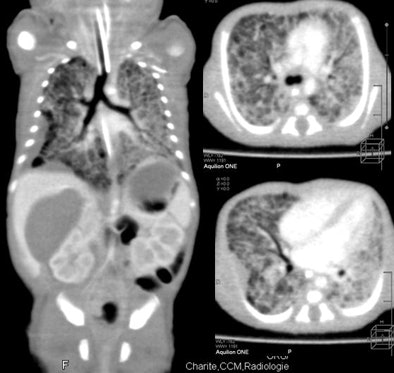

| Nearly whole-body imaging in a single rotation reveals lung changes and pleural thickening. |